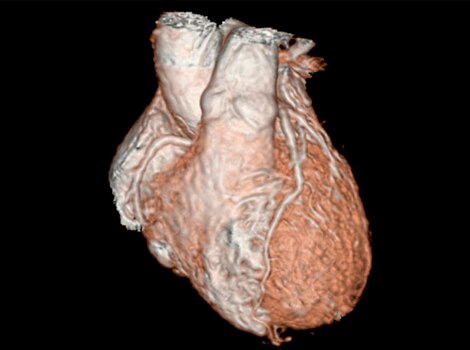

3D Heart

Visualize the anatomical structures and vascularity of the heart with a bright blood, 3D sequence.

Read More

Visualize the anatomical structures and vascularity of the heart with a bright blood, 3D sequence. Read More